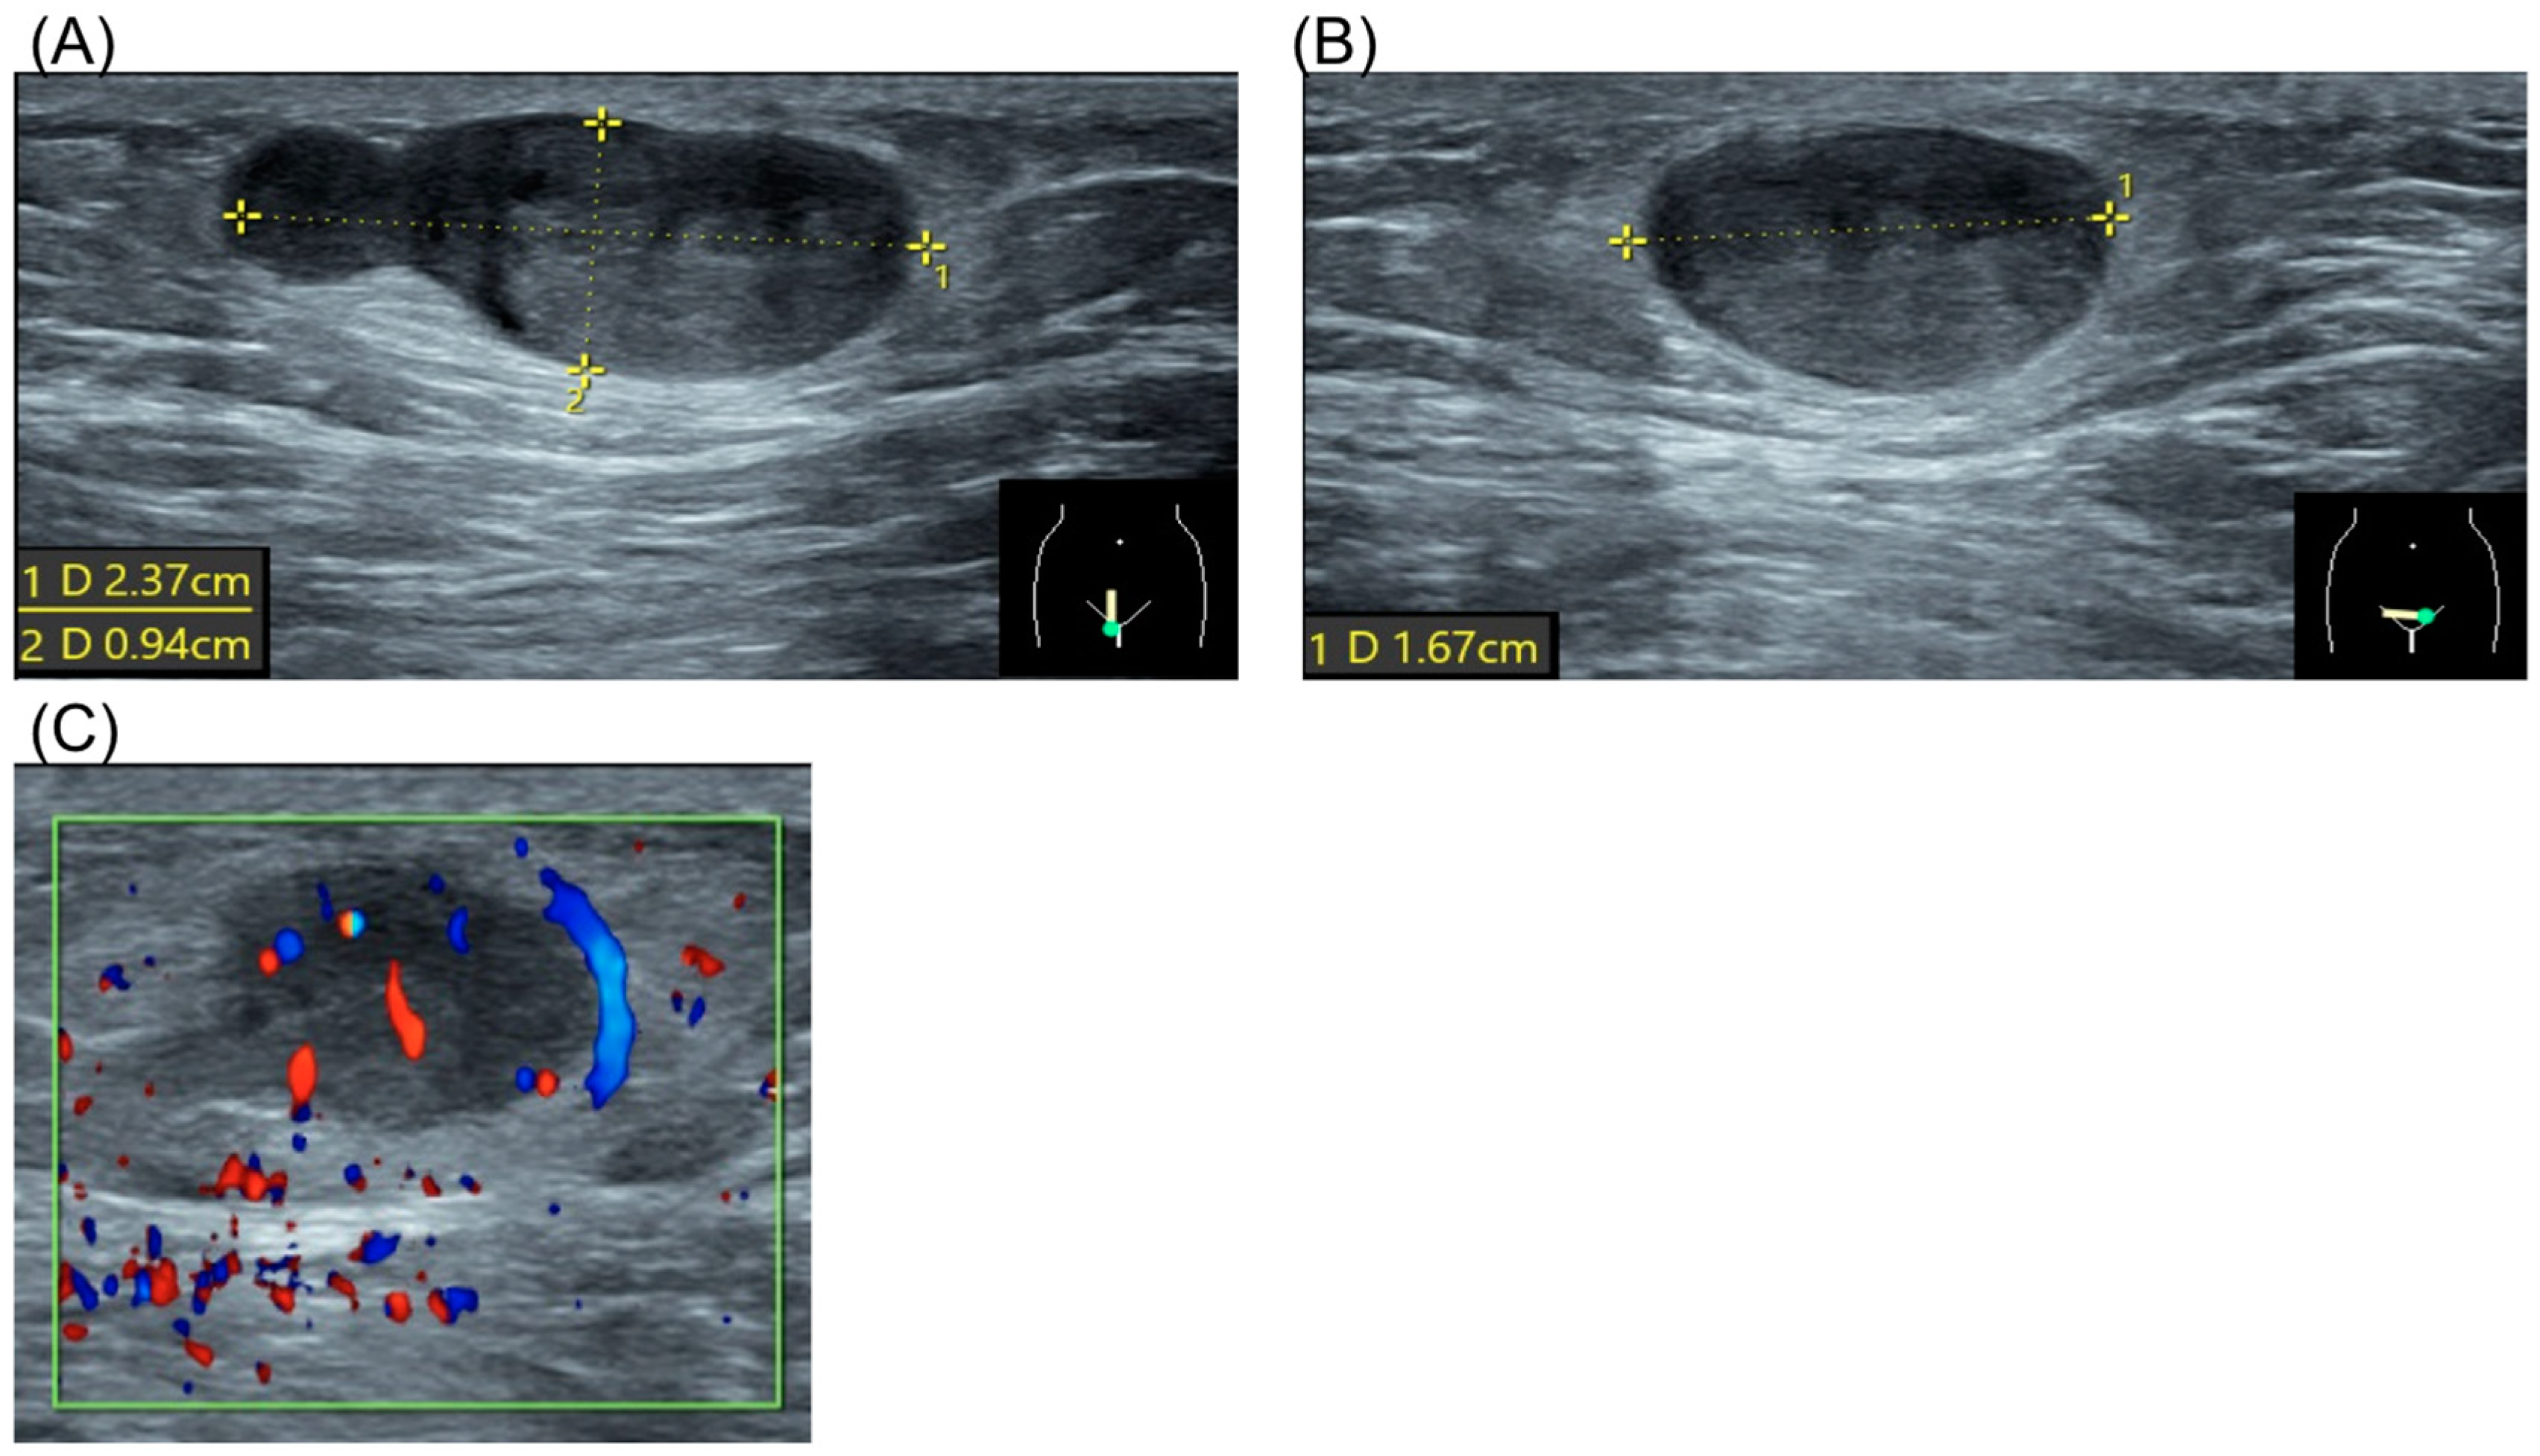

2. Case Report